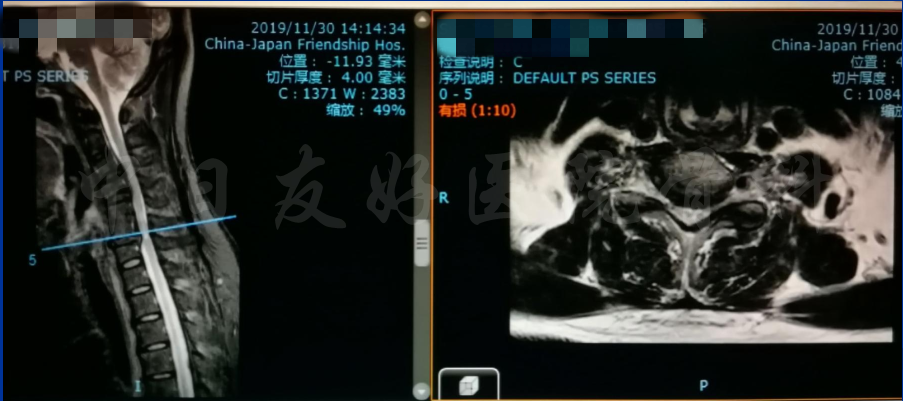

MRI

MRI颈4-5(左)、颈5-6(中)颈6-7(右)

矢状位MRI

轴位MRI:腰3-4(左)、腰4-5(中)、腰5骶1(右)

2019年11月30日 颈椎MRI提示:颈3/4颈4/5颈6/7椎间盘突出,椎管狭窄;颈5-6水平脊髓异常信号,变性可能。

颈椎MRI

颈椎MRI

颈椎各节段MRI(上下滑动)